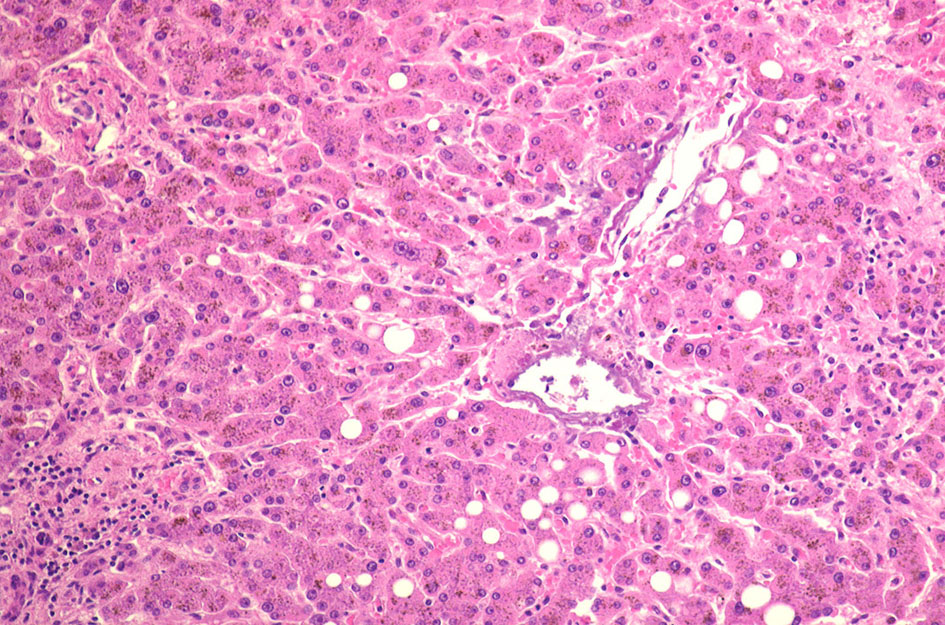

70歳代男性の骨髄。hypercellular marrow. M/E=1-2, erythropoietic hyperplasiaを認める(1, 2). megaloblastosisが出現。(3).

Mgkは成熟大型のものが多い(4). 単核, 小型球状核のMgkも認められる(5)

骨髄塗抹標本と組織(clot section)の鉄染色(クリックで大きな画像がみられます) ring sideroblastは鉄顆粒が核周囲にまとわりつくように見える赤芽球として認められる。Hb合成の乏しい幼若な大型赤芽球では認められる鉄顆粒は少ない。